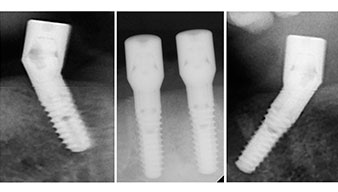

After removal of the residual dentition in the mandible, the alveolar crest was exposed from 37 to 47.

The mental foramen was first identified as a limiting anatomical structure and then the cortical bone of the crest was smoothed with the straight handpiece and a large rose-head bur (Fig. 4).

residual dentition

Fig. 4